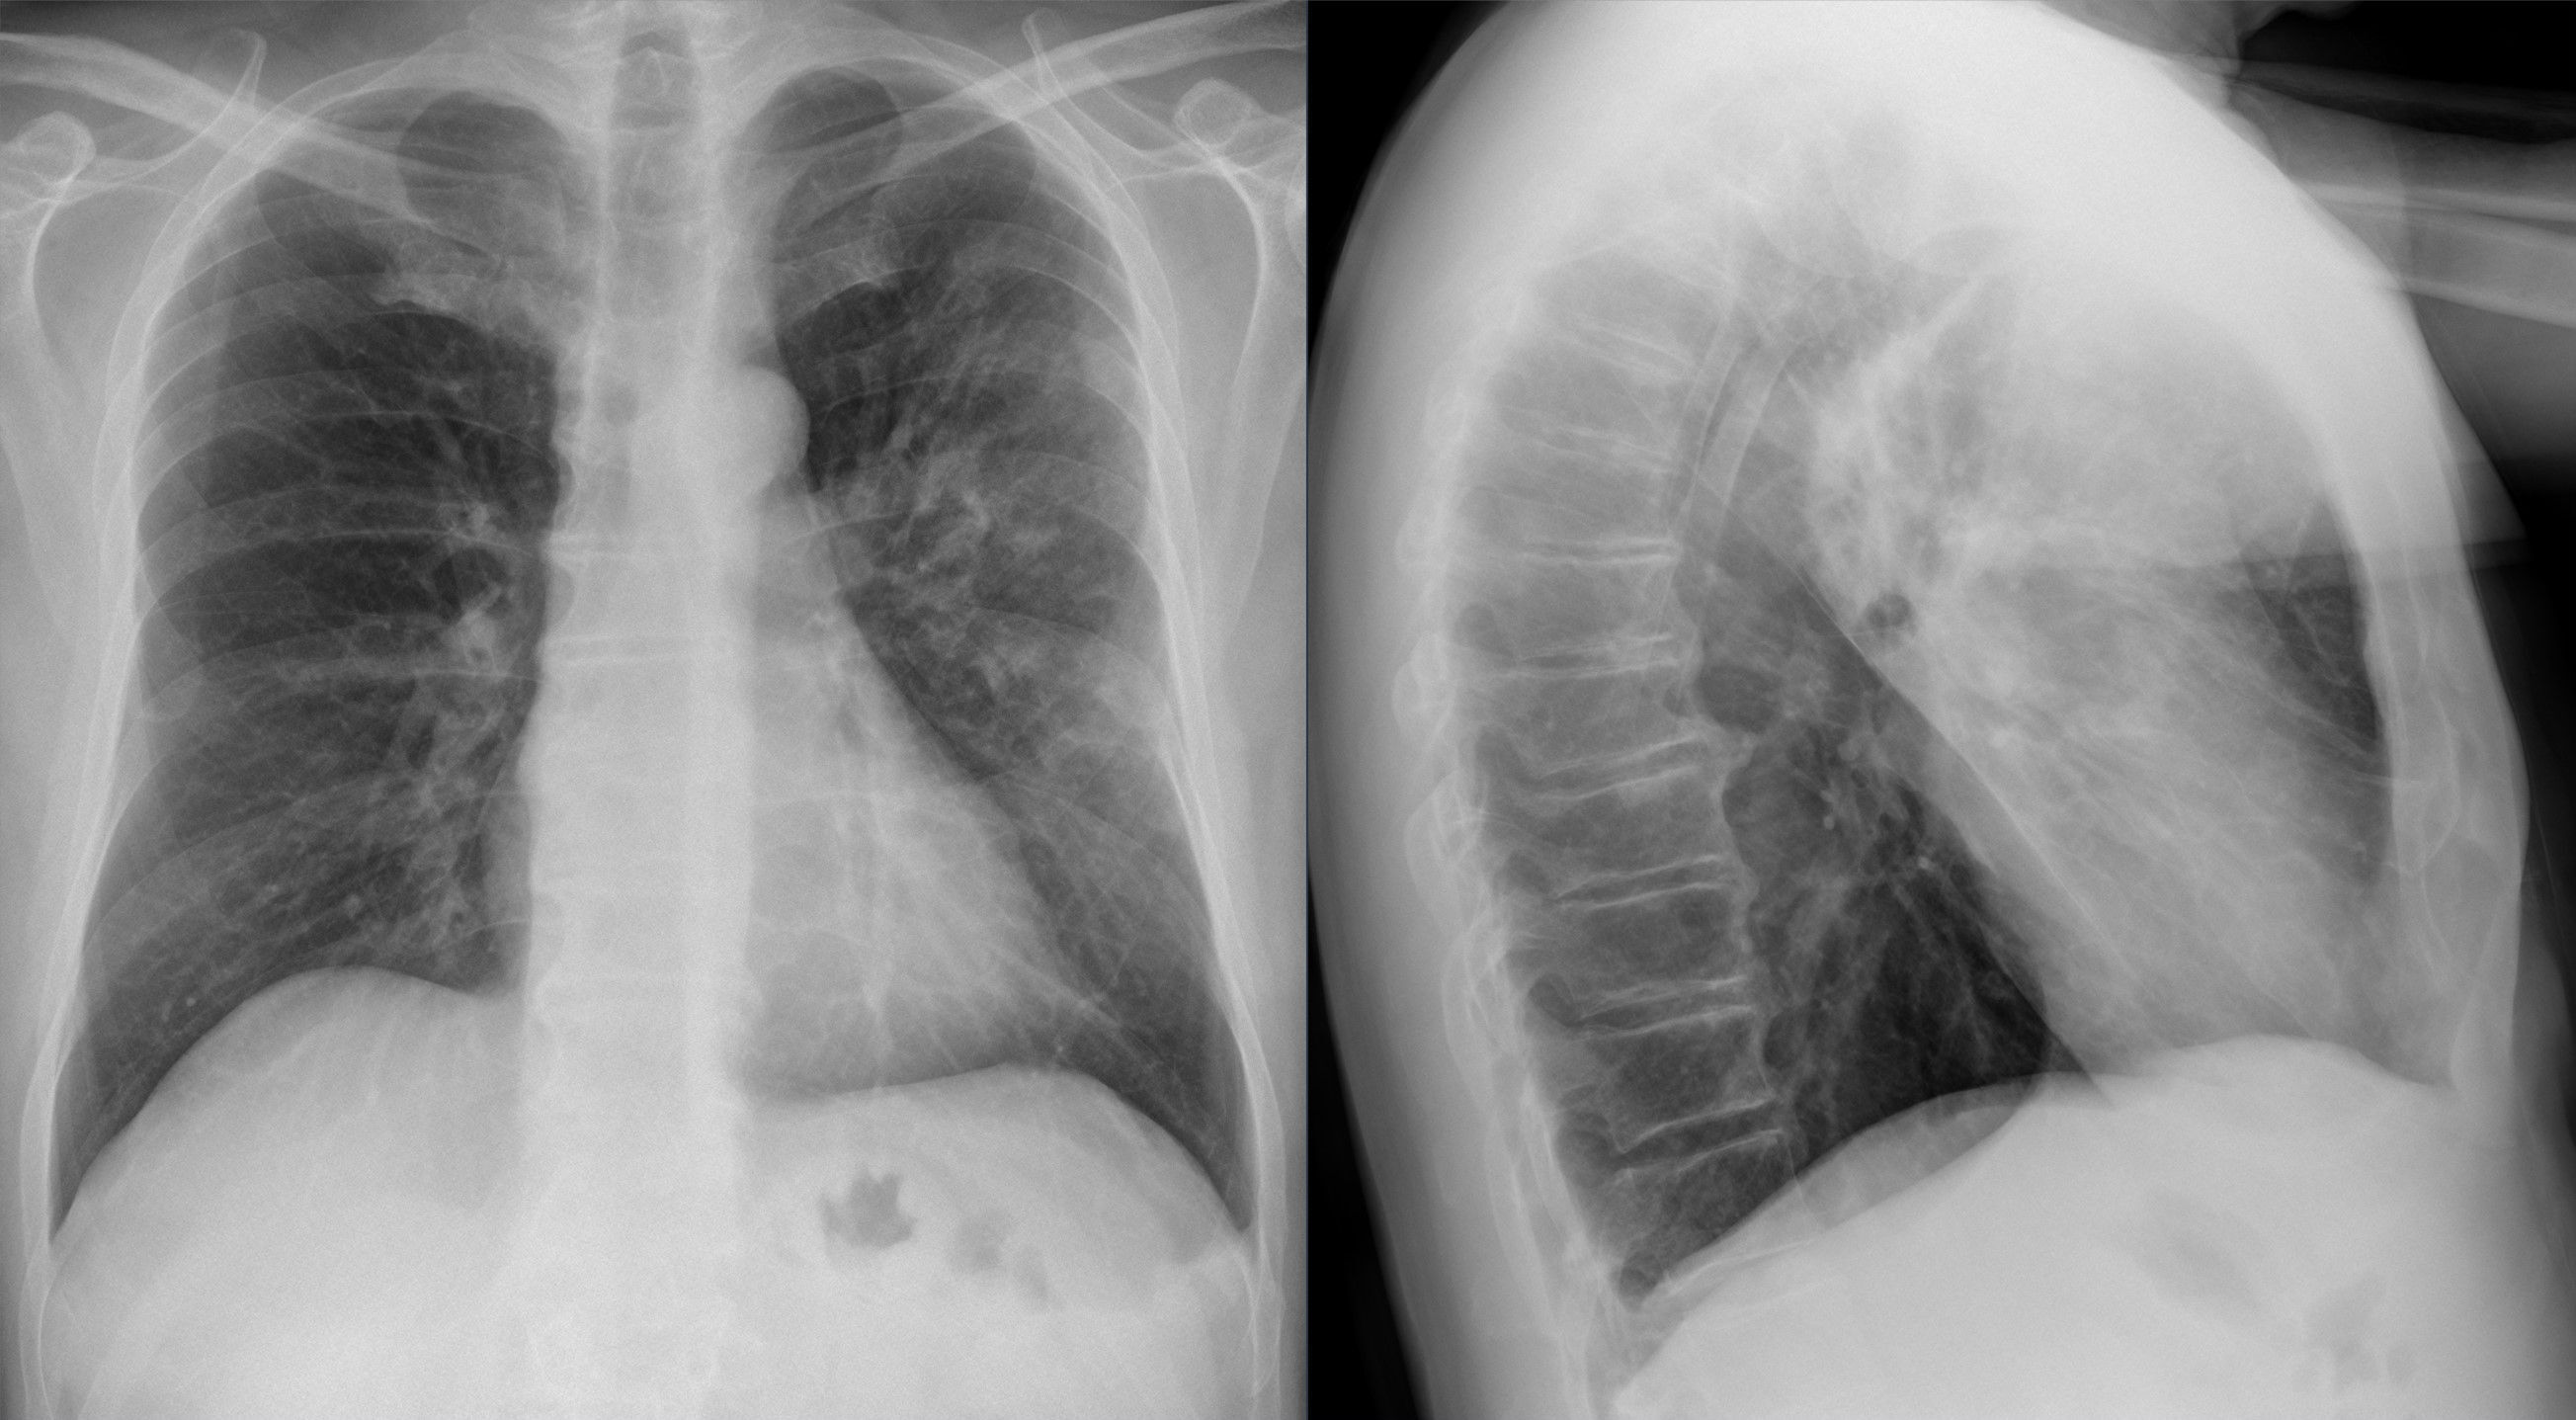

Также профессор отметила, что температура и кашель при простуде проходят за 5-7 дней, а при туберкулезе симптомы длятся недели или даже месяцы. Для диагностики проводят флюорографию.

Фото: commons.wikimedia.org, Hellerhoff, Creative Commons Attribution-Share Alike 4.0 International license.